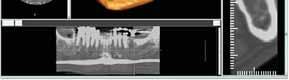

Case 2:

A 20 year old male was referred to Endodontic Department of Jahra Dental Speciality Centre for root canal treatment of lower right first mandibular molar. The referring dentist had done pulpotomy of the tooth. On examination, the tooth was slightly tender on percussion. Patient had no other symptoms and medical history was non contributory. Preoperative radiograph showed mandibular molar with one mesial and two distal roots. The distal root was with additional distolingual root. (Figure 5). Endodontic procedure was carried out under local anesthesia and rubber dam isolation. Initially two mesial and two distal canals were detected. The distal canal orifice was wide and opened to two separate canals. In mesial root after initial debridement of two canals, a bleeding spot remained in between the two canals which led to further exploration with a K file #08 and subsequently an intermediate canal was located. (Figure 6). Working length radiograph with distal angulation showed three mesial canals and two distal canals. (Figure 7). All the five canals were negotiated, working length determined, biomechanical preparation was carried out followed by obturation. (Figure 8). The patient was followed up.

Figure 1- Pre operative radiograph showing distal caries. Figure 2- Pulp chamber floor showing three independant mesial and two distal orifices. Figure 5- Pre operative radiograph showing mesial root and a distal root with an additional indistinct distolingual root. Figure 6- Pulp chamber showing three mesial and two distal canal orifices. Figure 7- Working length radiograph taken with distal shift technique. Figure 8- Post operative obturation radiograph showing three mesial and two separate distal roots. Figure 3 - Working length radiograph reveals three canals in the mesial root and two canals in the distal root. Figure 4- Post operative obturation radiograph.